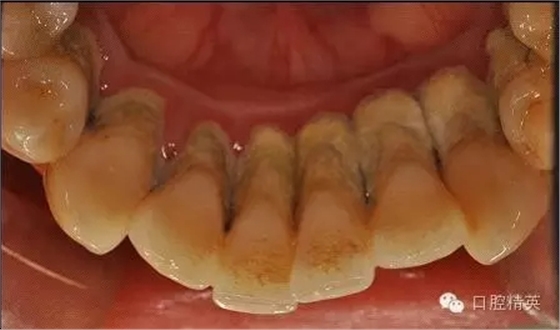

本病例 :女 34歲,主訴刷牙出血,覺牙齒輕度松動一年。

檢查見大量齦上及齦下結(jié)石,探診出血,牙周袋較深,32-42 II度松動。X線片顯示牙槽骨水平吸收。

診斷:成人慢性廣泛性中度牙周炎。

治療前: